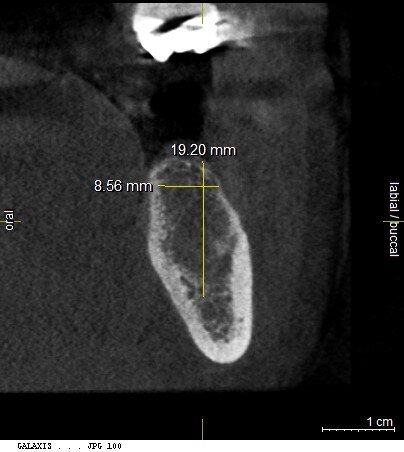

The patient, a 67-year-old non-smoking man without any relevant medical history, was referred to the office with a missing tooth (#36) due to persistent apical periodontitis. The tooth had been extracted more than one year prior to the procedure and the molar site was well maintained and fully healed (Fig. 1). A CBCT scan showed that the patient had favourable bone availability (Fig. 2), on which basis a one-stage placement of a 5.5 × 10.0 mm Straumann BLX implant was planned. After surgically installing the implant (Figs. 3–7), Salvesen allowed the surrounding soft tissue to mature and heal for six weeks (Fig. 8). He then removed the healing abutment to begin the prosthetic procedures for a temporary crown (Figs. 9 & 10). A stone master cast was made in the laboratory, and a temporary screw-retained PMMA crown was manufactured over a Straumann wide base temporary abutment for the crown (Fig. 11) and placed on to the implant (Figs. 12–14).

Fig. 4: Implant insertion with the handpiece at 15 rpm.